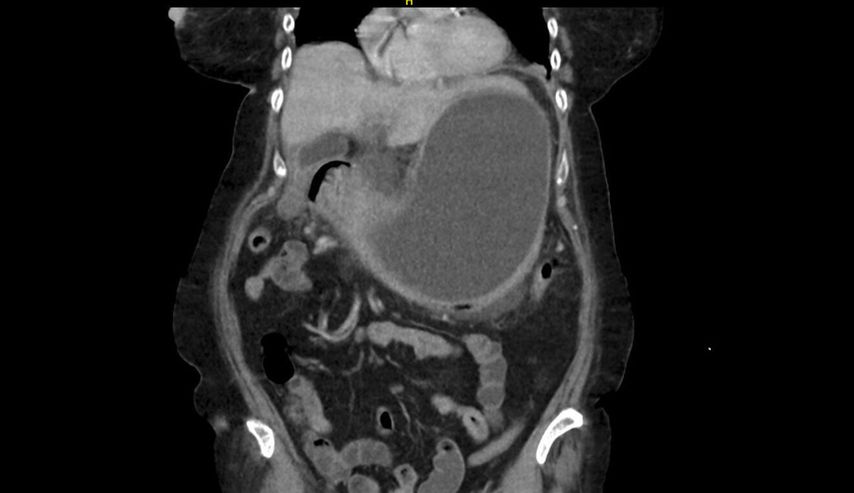

In der durchgeführten Computertomografie des Abdomens (Abb.1) zeigt sich der Verdacht auf einen hohen Ileus mit prall sekretgefülltem, distendiertem Magen (25cm kraniokaudal). Weiters stellt sich die Magenwand auf bis zu 17mm verdickt dar – mit intramuralen Lufteinschlüssen, insbesondere entlang der großen Kurvatur. Eine Ausgangsstenose im gastroduodenalen Übergang wird suspiziert. Rasch wird eine nasogastrale Sonde eingebracht, die trotz korrekter Lage kein Sekret fördert.